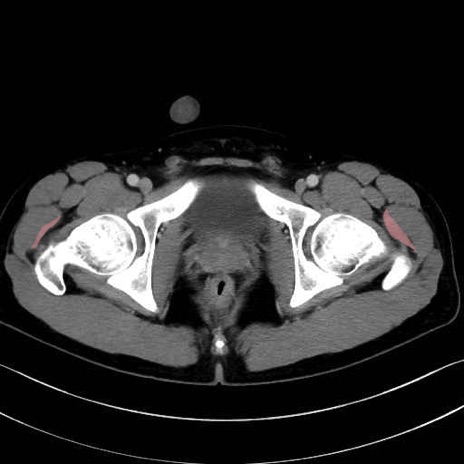

小殿筋 (Gluteus minimus)